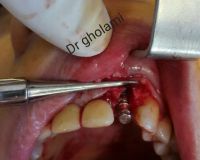

معرفی سیستم SPI همراه با جراحی زنده و Immediate Loading - آبان ۹۵

جراح وسخنران : استاد دکتر غلامعلی غلامی